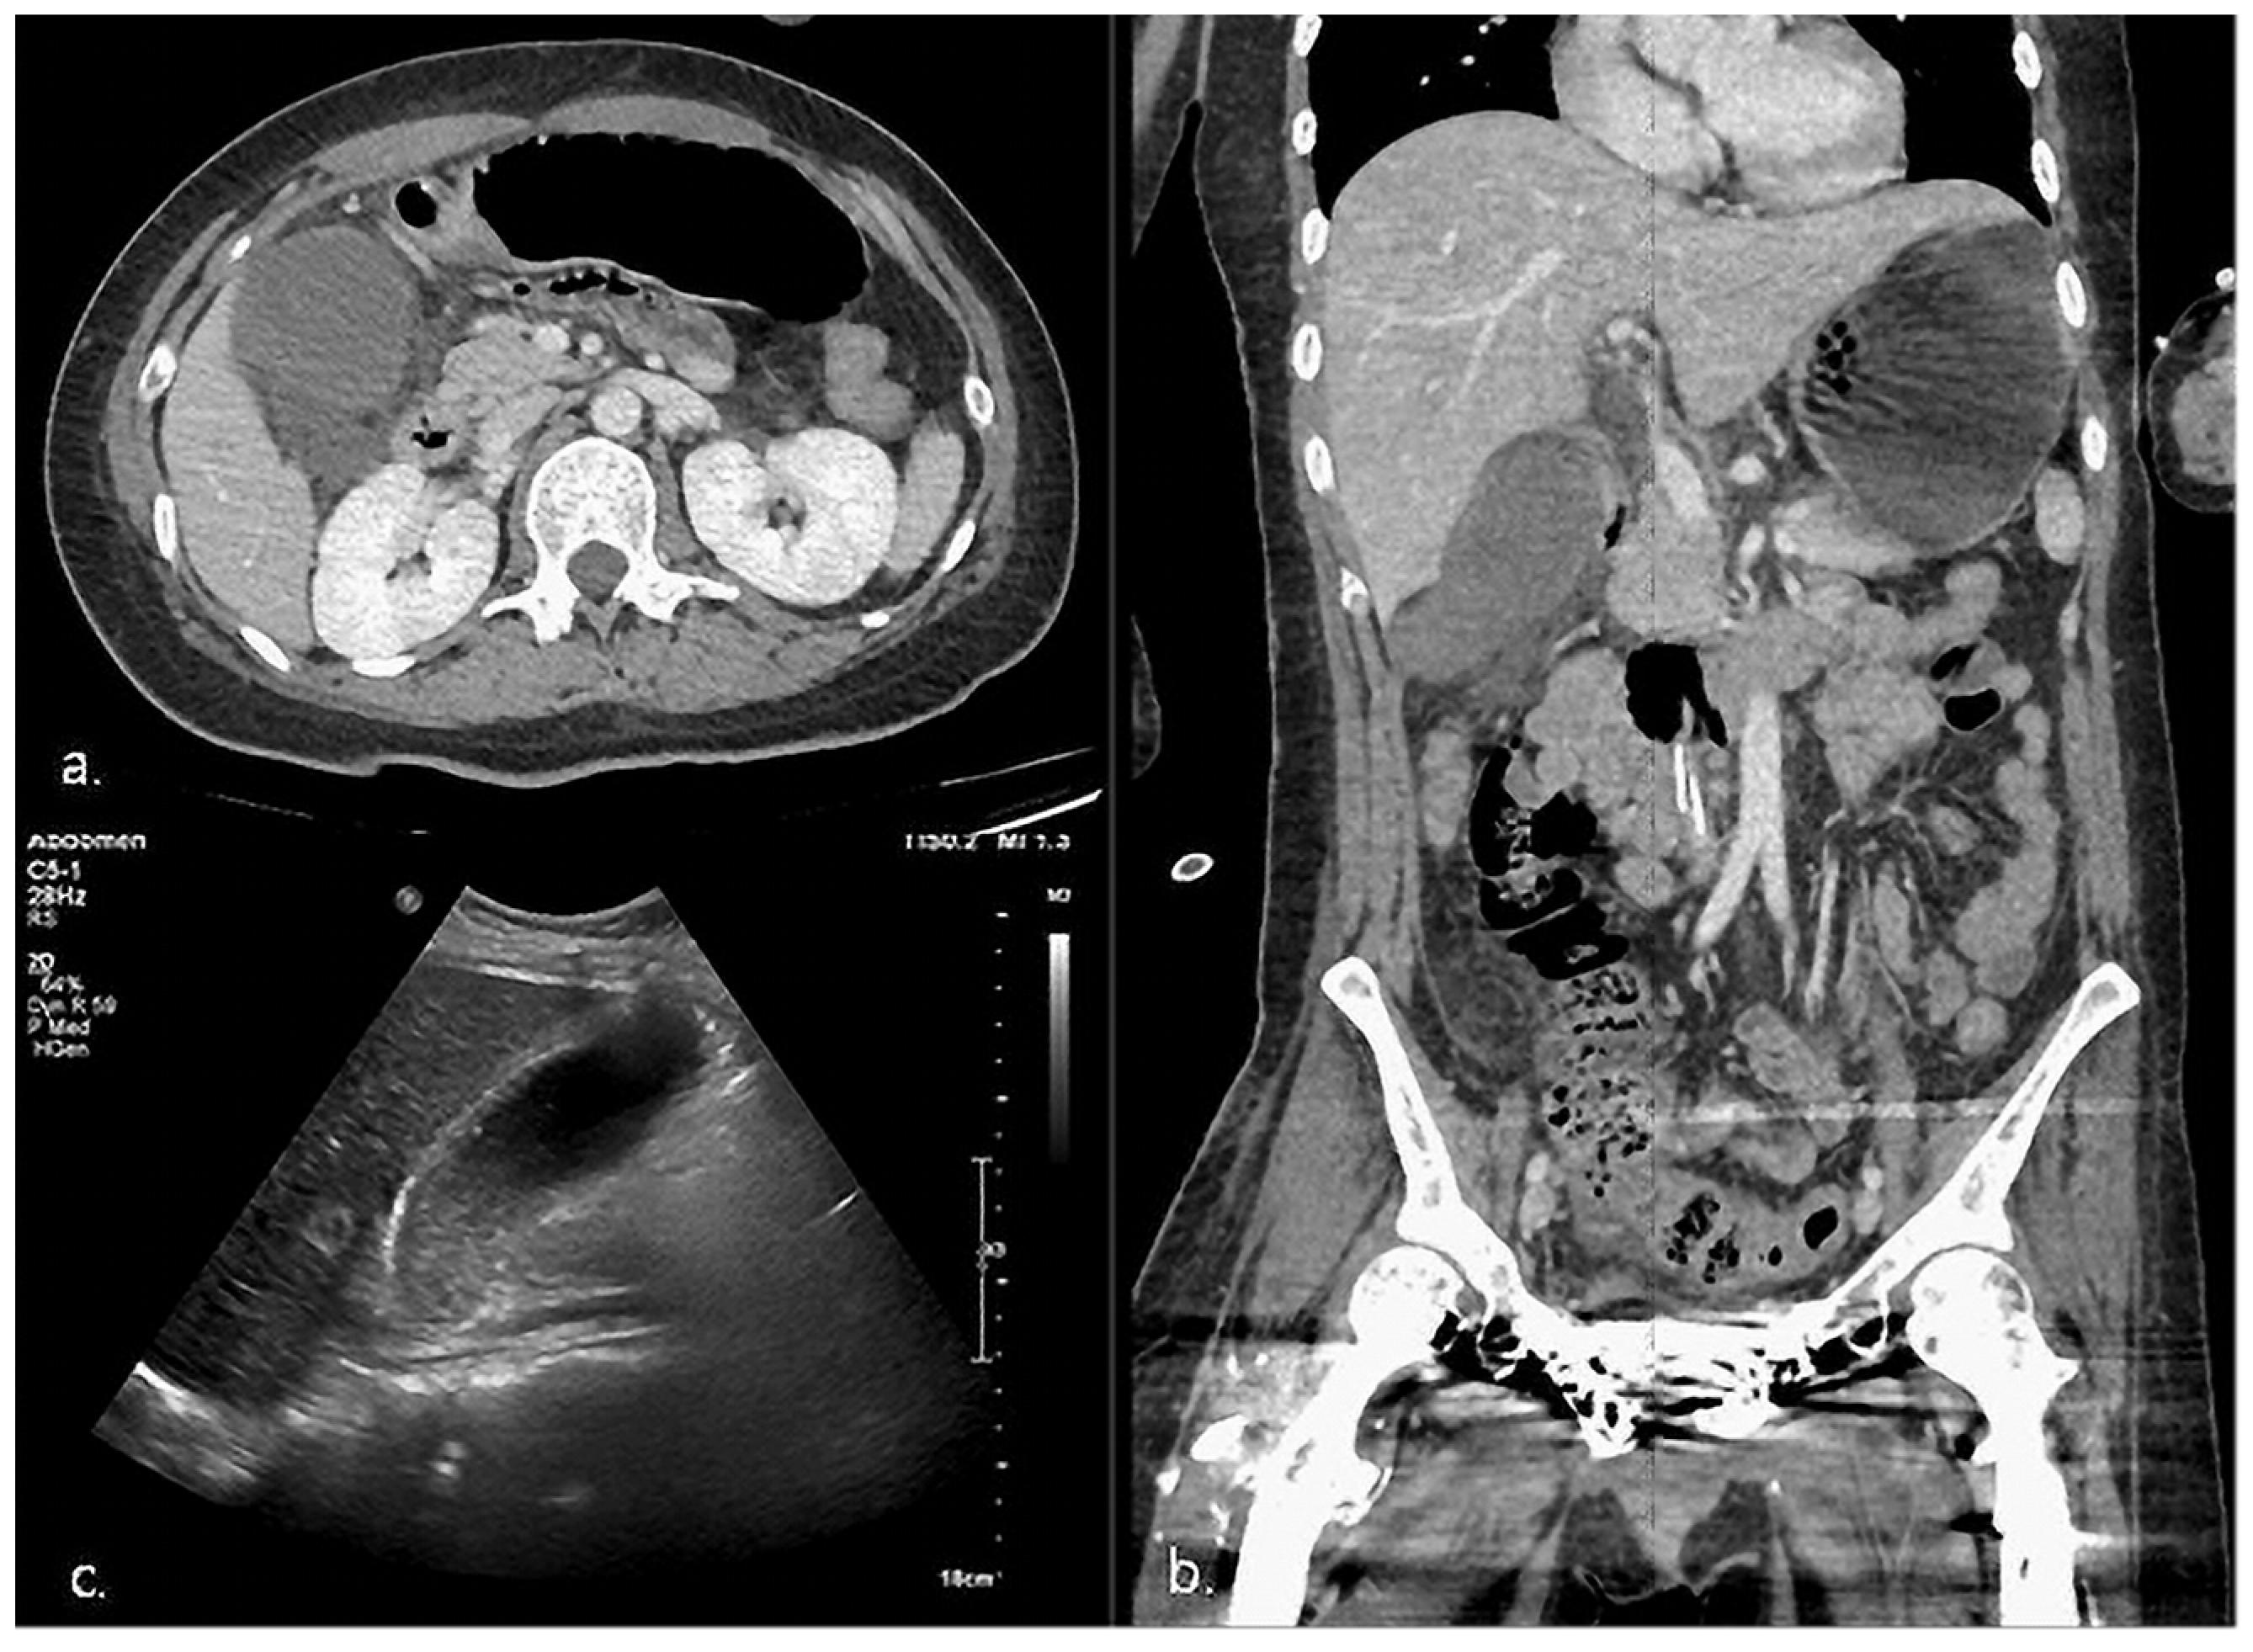

| 1 | HD 65 | 1 | Epigastric discomfort RLQ tenderness Murphy’s sign * | Fever * Elevated CRP *, WBC * | CT, US | 93 × 41 * | 3.76 | (+) * | (−) | Definite AC |

| 2 | HD 105 | 4 | RUQ tenderness * | Fever Elevated CRP * | CT, US | 78 × 49 | 4.1 * | (+) * | (−) | Definite AC |